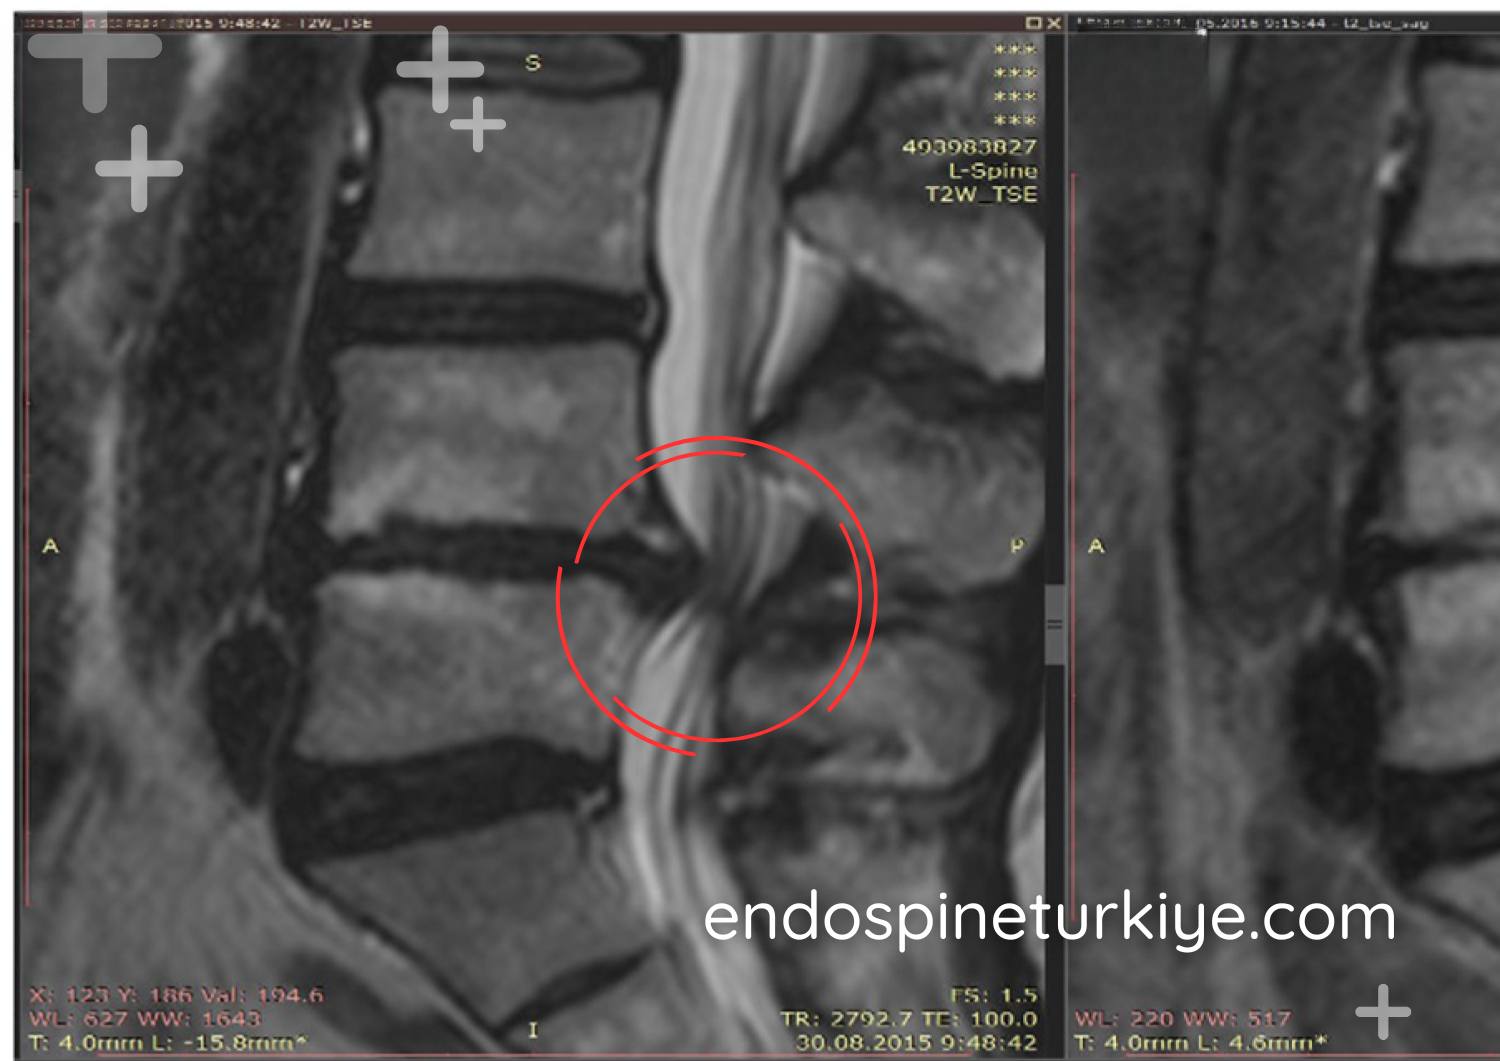

Ameliyat korkusundan son 1 yıl içinde her yöntemi denemiş ve sonuç alamamış biri olarak, Op. Dr. Rifat Saygın Altınağ'a tam kapalı endoskopik disk ameliyatı olalı 1 ay oldu. Birçok doktora gitmeme rağmen beni ikna eden tek kişi olduğu için güvenle ameliyatı kabul ettim. Çevremde açık ameliyat olup sorun yaşayanlar vardı. Rifat Bey'e gidene kadar tam kapalı ameliyatın mümkün olduğunu bilmiyordum. Şiddetli bacak ağrısından yürüyemeyen ben, şimdi normal hayatıma döndüm. Ameliyat sonrası 5 saat içinde hastanede korseyle yürümeye başladım. Kendimi o kadar iyi hissediyordum ki hastanede dolaştım. İyileşmeyi bekleyip yorum yazdım, bugün kontrolle tescillendi. Rifat Bey'e ve Merve Hanım'a teşekkürler.